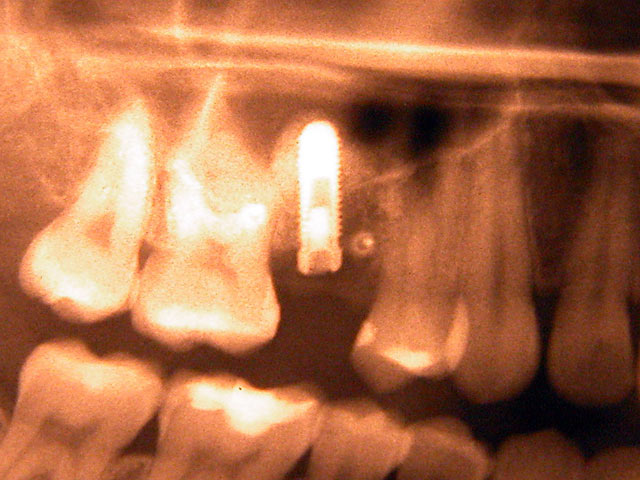

Die folgenden Patientenfälle sollen Ihnen einen Einblick in die Möglichkeiten der modernen Implantation geben.

Implantation mit externem Sinuslift: